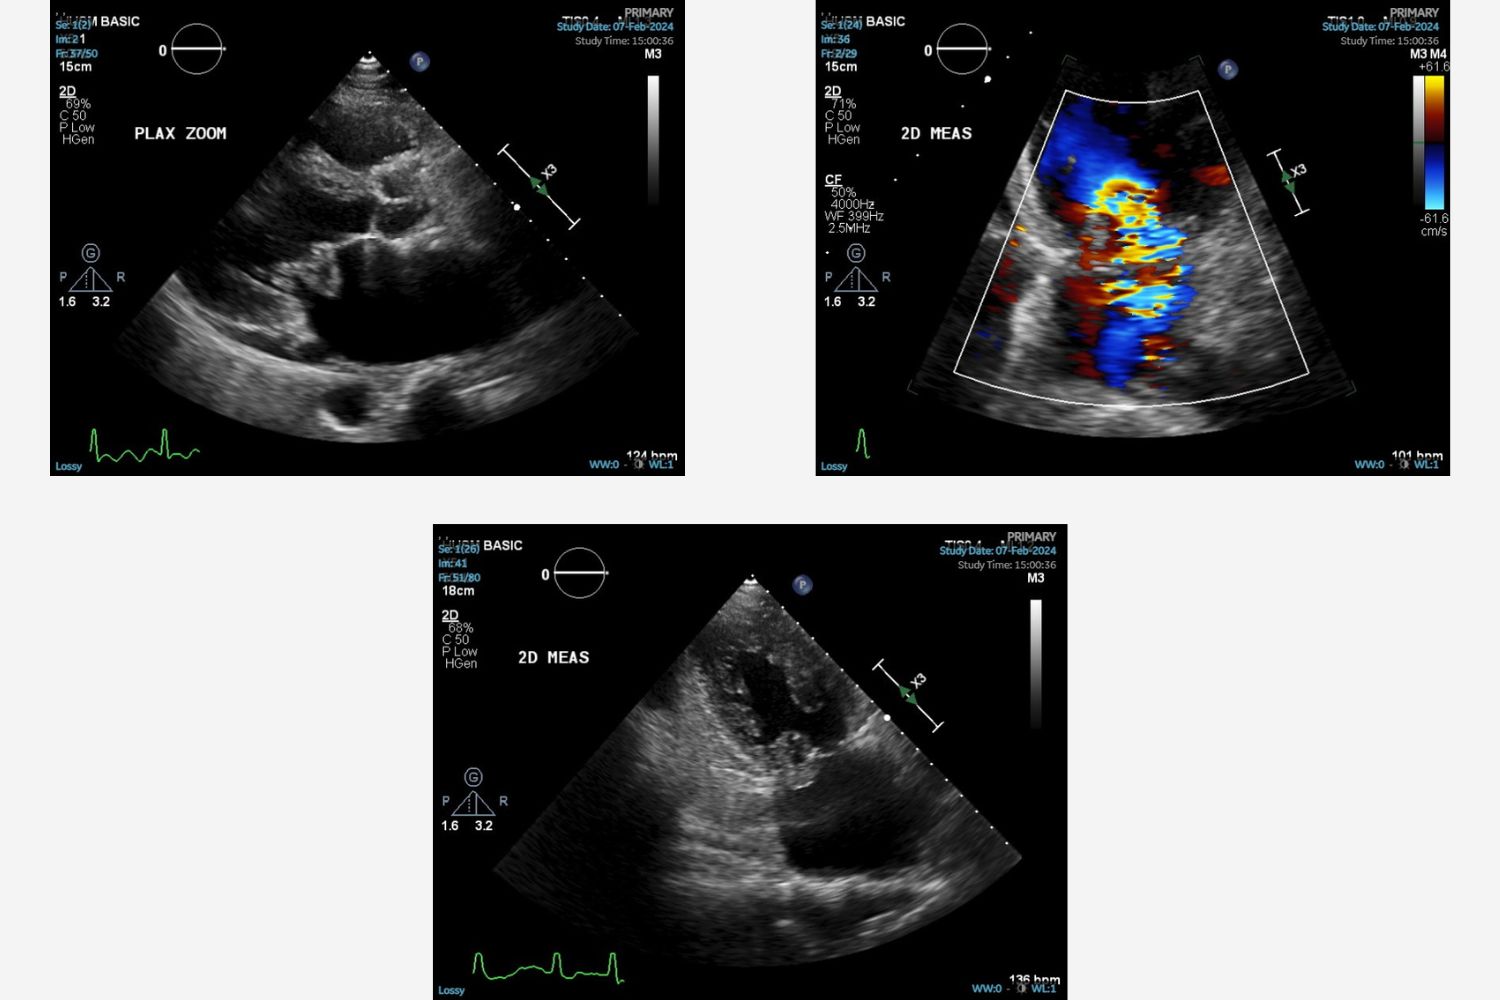

Image of the Week - 8 May 2024

Doctor Vijay Soorampally

Doctor Bharath Raj Kidambi

Doctor Sriram Veeraraghavan